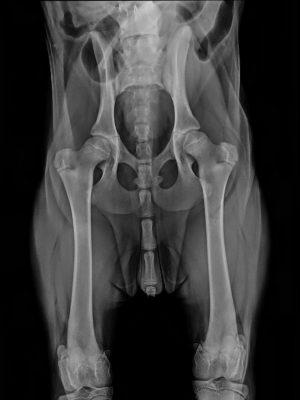

Zastosowanie rentgenografii w diagnostyce

Zdjęcia rentgenowskie stanowią niezwykle wartościowe narzędzie w diagnozowaniu wielu chorób. Wykorzystywane są przede wszystkim w przypadku problemów ortopedycznych (głownie związanych z kończynami piersiowymi, miednicznymi czy kręgosłupem). Rentgenografia pozwala również na wykrywanie ciał obcych, kamicy oraz zaczopowań w układzie pokarmowym i moczowym. Ponadto, jest to niezbędna metoda w diagnostyce chorób układu oddechowego, obejmujących szyję i klatkę piersiową. Współczesna medycyna korzysta z radiografii cyfrowej bezpośredniej (DR), która wymaga mniejszej ilości powtórzeń zdjęć. Dzięki temu pacjent jest wystawiony na niższą dawkę promieniowania, co przekłada się na większe bezpieczeństwo badania. Detektory DR charakteryzują się podwyższoną czułością, co pozwala na zastosowanie o około 30% mniejszej dawki promieniowania niż w przypadku tradycyjnej kliszy RTG.

Radiografia cyfrowa bezpośrednia

Radiografia cyfrowa bezpośrednia (DR) to nowoczesna technologia umożliwiająca uzyskanie wysokiej jakości obrazów rentgenowskich. W porównaniu do tradycyjnej kliszy RTG DR wykazuje szereg zalet, m. in. takich jak szybkość przetwarzania obrazu czy możliwość jego poprawy za pomocą oprogramowania. Dzięki temu można uniknąć konieczności powtarzania zdjęć, co przekłada się na mniejszą ekspozycję pacjenta na promieniowanie. Proces poprawy obrazu za pomocą oprogramowania pozwala na wyeliminowanie niedoskonałości wynikających z prześwietlenia lub niedoświetlenia zdjęcia. Detektory DR są bardziej czułe niż tradycyjne klisze, co umożliwia redukcję dawki promieniowania o około 30%. To istotne z punktu widzenia bezpieczeństwa zarówno pacjentów, jak i personelu medycznego.